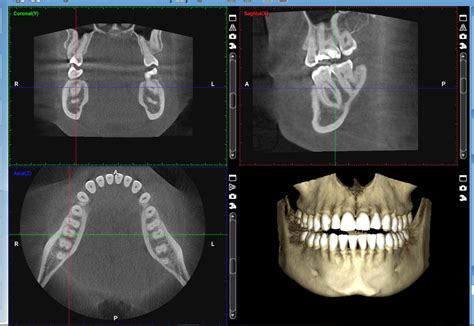

La exploración mediante tac dental o tomografía computarizada para el diagnóstico maxilofacial debe ser efectuada con equipos que dispongan de programas informáticos de reformación multiplanar (MPR). La tomografía computarizada de haz cónico (TCHC), más comunmente conocida por sus siglas inglesas (CBCT, cone beam computed tomography), que también se conoce como 3D gracias a su capacidad para generar imágenes tridimensionales, es, indudablemente, la técnica de diagnóstico por imagen con mayor proyección actualmente.

El Cone beam o CBCT (Cone Beam Computed Tomography), llamado también tomografía volumétrica digital de haz cónico, es una técnica de imagen seccional en 3D en pleno auge. Como su nombre indica, el tac dental consiste en un generador de rayos X que emite un haz de irradiación abierto de forma cónica que, en una rotación completa (360º) o semicompleta (180º), permite recorrer todo el volumen a explorar antes de analizarlo tras atenuar los rayos mediante un sistema de detección.

- Endodoncia: Facilita la observación de los conductos a tratar, su longitud y la existencia de conductos adicionales.

- Ortodoncia: Para valorar la posición de dientes incluidos o supernumerarios, y en la planificación de tratamientos de ortodoncia invisible.